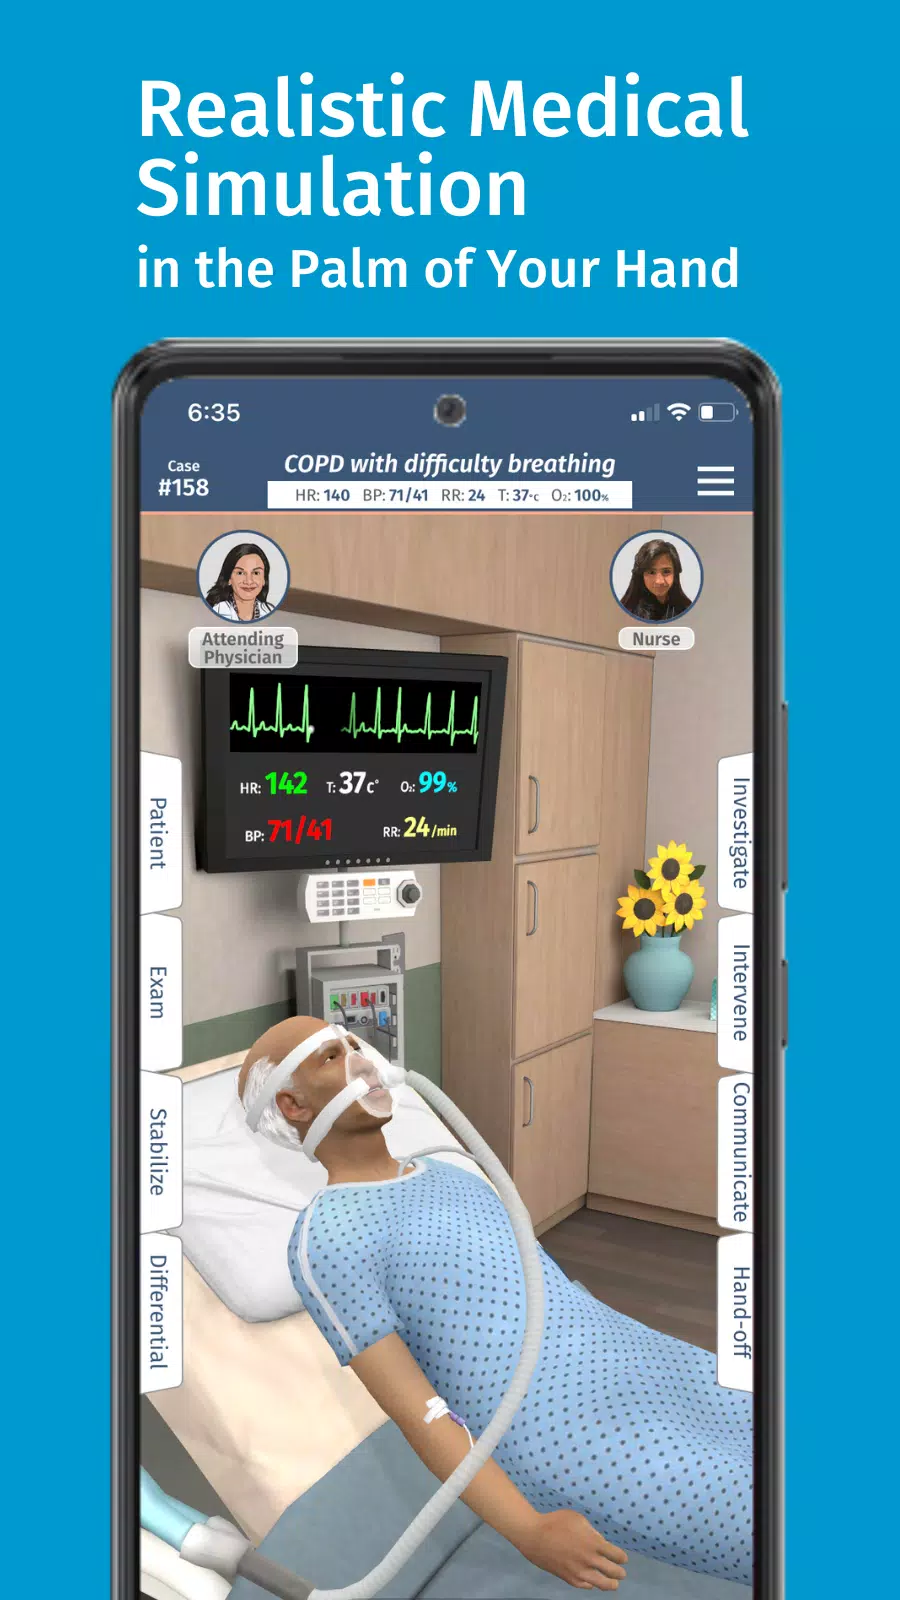

သင်သည်သင်၏အလုပ်များသောအချိန်ဇယားနှင့်ကိုက်ညီသောစွဲမက်ဖွယ်ကောင်းသောဆေးဘက်ဆိုင်ရာလေ့ကျင့်မှုများကိုရှာဖွေနေပါသလား။ အပြည့်အဝကုဒ်များထက်မကြည့်ပါနှင့်။ ဆေးဘက်ဆိုင်ရာသင်ယူသူများအတွက်ဒီဇိုင်း - အစွန်း virtual virtual simulation platform ။ ဘယ်နေရာမှာမဆို, ဘယ်နေရာမှာမဆို, ဘယ်နေရာမှာမဆိုအပြည့်အဝကုဒ်သည်လက်တွေ့ကျသော, သင်သည်သင်၏ပထမဆုံးဆေးကျောင်း၏ပထမနှစ်ကိုသွားလာသည်ဖြစ်စေ Residency အတွက်ပြင်ဆင်ခြင်းသို့မဟုတ်သင်၏လက်ရှိကျွမ်းကျင်မှုများကိုမြှင့်တင်ရန်ရှာဖွေခြင်း,

ကုဒ်အပြည့်အဝ code ၏တောင်းဆိုခြင်းခြင်း simulation လေ့ကျင့်ရေးလေ့ကျင့်ရေးနှင့်အတူရှုပ်ထွေးသောဆေးဘက်ဆိုင်ရာကိစ္စရပ်များလေ့ကျင့်နိုင်ပြီးသင့်အားအခိုက်အတန့်ရှိသည့်အခါတိုင်းသင်၏ဆေးခန်းကျွမ်းကျင်မှုများကို Hone နိုင်သည်။ မိုဘိုင်းထုတ်ကုန်များအတွက်ဒီဇိုင်းရေးဆွဲထားသည့်ကုဒ်အပြည့်အ 0 သည်သင်ပိုင်ဆိုင်ပြီးသောကိရိယာများကို အသုံးပြု. သွားလာရန်နှင့်တိုးတက်ရန်ခွင့်ပြုသည်။

အမေရိကန်ဆေးရုံများကို ဦး ဆောင်ခြင်းနှင့်လိုင်စင်ရပညာရှင်များ၏တင်းကြပ်စွာပြန်လည်သုံးသပ်ခြင်းမှဆေးကုသမှုဆိုင်ရာပညာရှင်များကတီထွင်ခြင်းဖြင့်တီထွင်ထုတ်လုပ်နိုင်ပြီး Code ၏ Simulats သည်စက်မှုလုပ်ငန်းဆိုင်ရာအကောင်းဆုံးအလေ့အကျင့်များကိုလိုက်နာသည်။ ၎င်းသည်ကျွန်ုပ်တို့၏ကမ္ဘာလုံးဆိုင်ရာသင်ယူသူအသိုင်းအဝိုင်းအတွက်အရည်အသွေးမြင့်သင်ယူမှုအတွေ့အကြုံကိုသေချာစေသည်။

အပြည့်အဝကုဒ်အကန့်အသတ်မဲ့ထပ်ခါတလဲလဲဖြစ်ရပ်များသည်သင့်အားရောဂါရှာဖွေခြင်းနှင့်စီမံခန့်ခွဲမှုနှစ်ခုလုံးကိုလက်တွေ့ကျင့်သုံးရန်ခွင့်ပြုသည်။ ၎င်းသည်သင့်အားရှုပ်ထွေးသောအစစ်အမှန်ကမ္ဘာကြီးကိုယုံကြည်မှုတိုးများလာစေရန်သင့်အားပြင်ဆင်သည်။